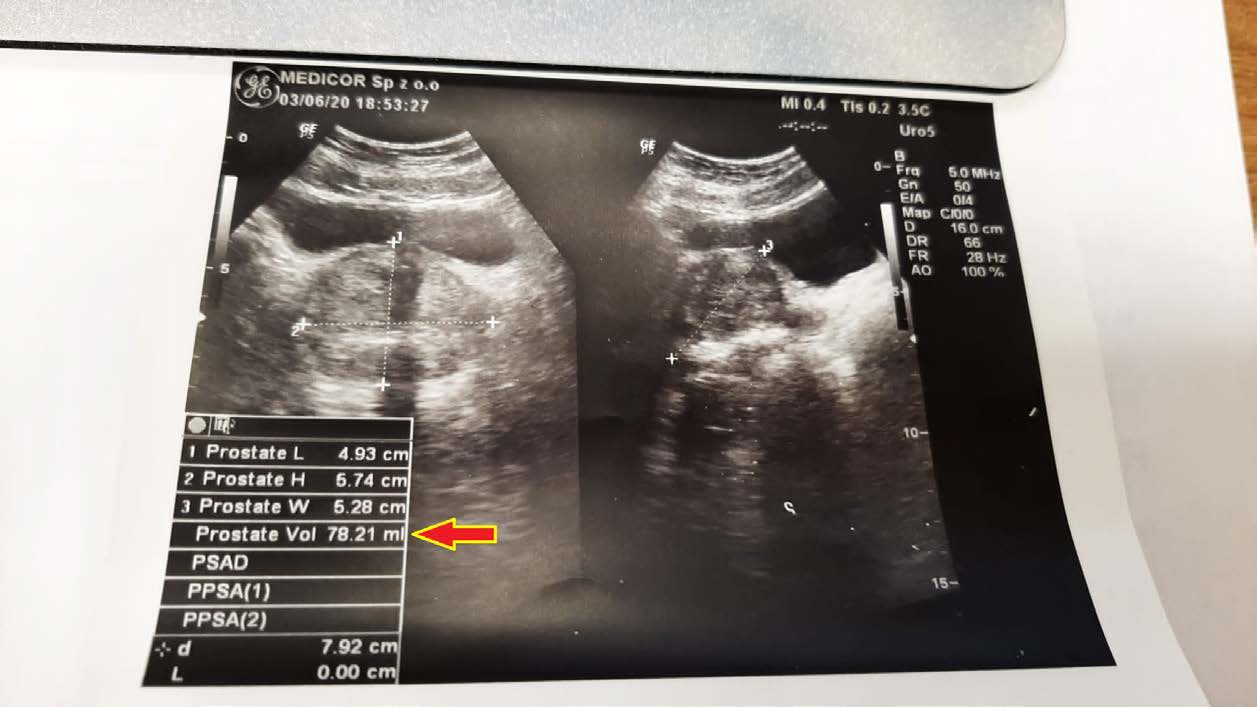

EFEKT PREPARATU NA PRZEROST GRUCZOŁU KROKOWEGO

Mężczyzna lat 50 z przerostem gruczołu krokowego, mimo iż to łagodna hiperplazja, odczuwał ból i dyskomfort przy oddawaniu moczu. Objętość gruczołu krokowego w dniu diagnozy wynosiła 78,21 ml (78,21 cm3). Po nieudanych próbach z finasterydem, podjęto próbę zmniejszenia gruczołu preparatem, jak widać ze zdjęć kontrolnych USG z sukcesem – znaczne zmniejszenie już po 2,5 miesiąca terapii do 55,97 ml (55,97 cm3).